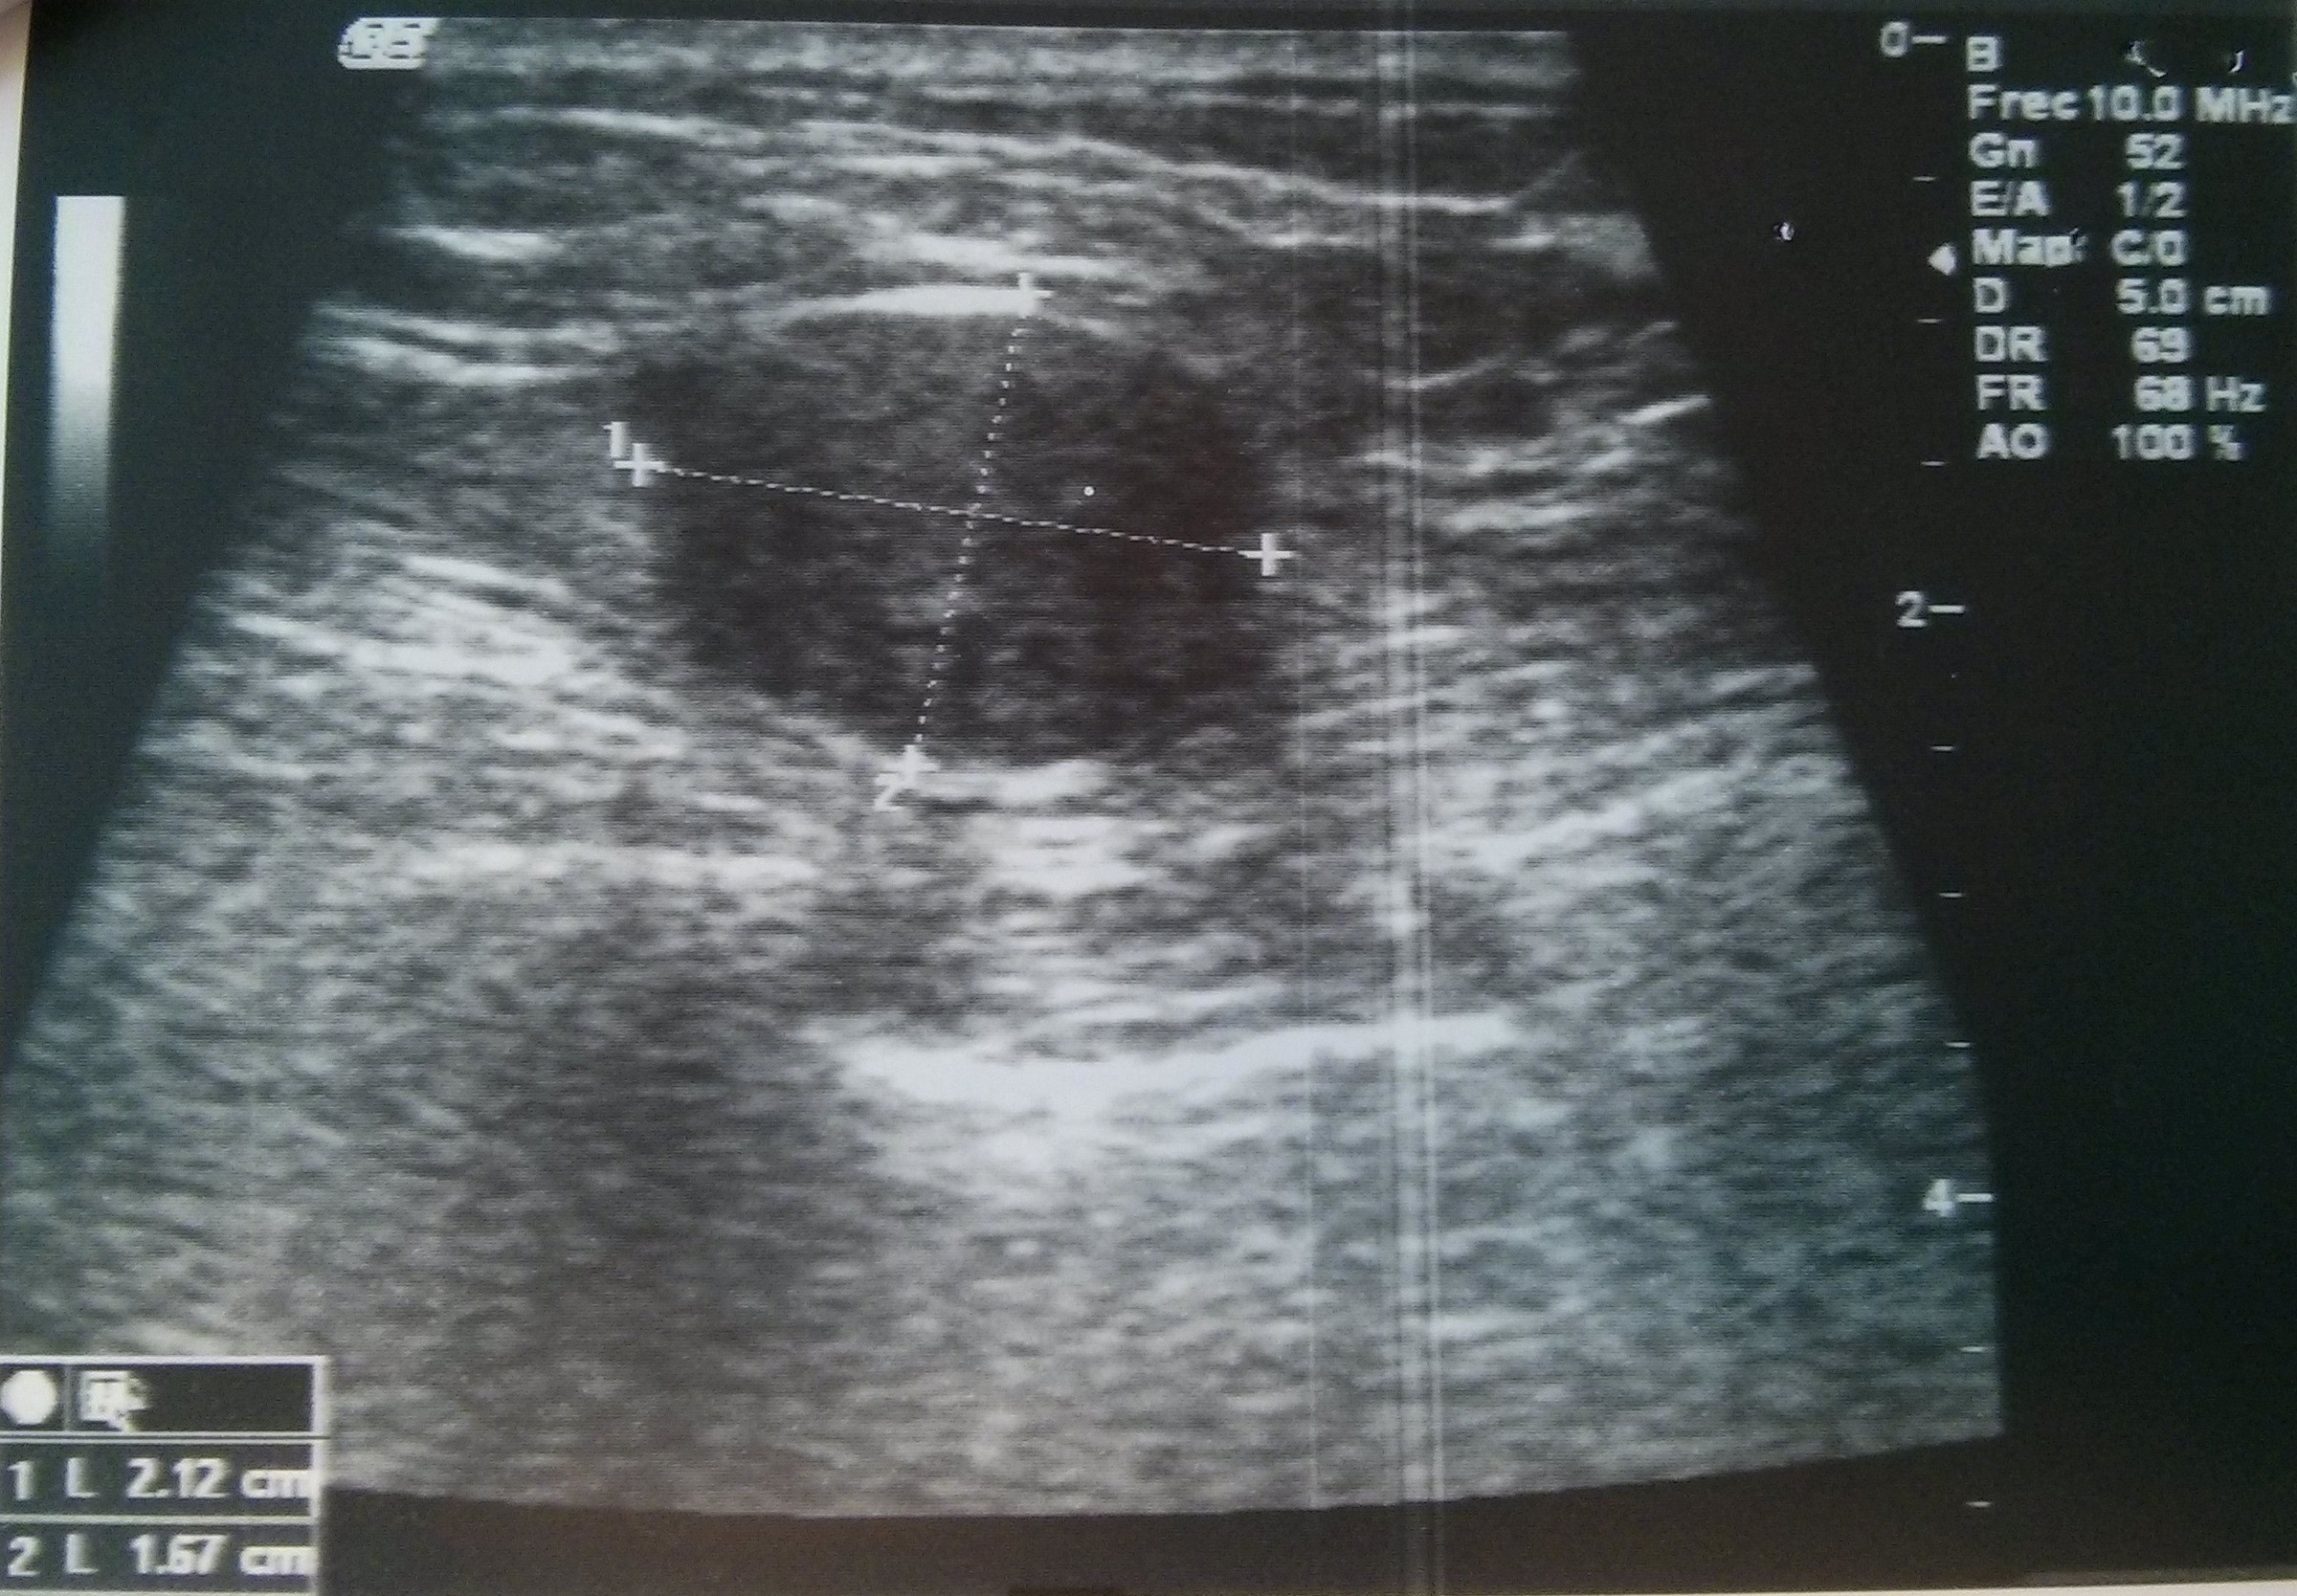

Paciente varón de 54 años con tumoración en unión de cuadrantes superiores de mama izquierda que parece depender del músculo. Se realiza punción con aguja fina.

Se adjunta fotografías de las extensiones, bloque celular y mamografía y ecografía.